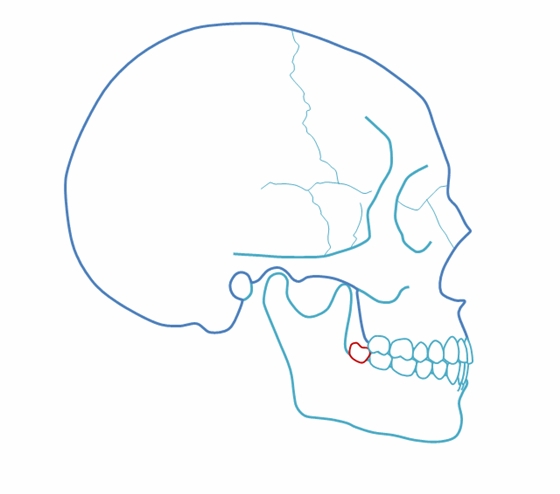

完全埋在牙槽骨里的下頜智齒,它本身倒是不出問題。但是這些近中或水平阻生的智齒,會推擠下頜第二磨牙,導致第二磨牙伸長:

然后,第二磨牙造成咬合干擾、早接觸,前牙開 牙合…………

甚至髁突吸收:

所以,這種智齒也還是要拔掉。